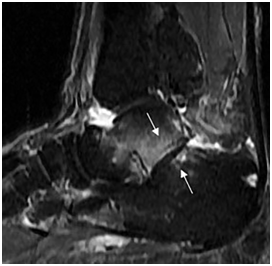

MRI also revealed subtalar degeneration as narrowing of the joint space, subchondral trabecular edema, and cystic changes on sagittal images (Figure 3). Flexor hallucis longus tendon was displaced and entrapped by the exophytic tumor (Figure 4).

Figure 3 Sagittal fast spin-echo T2W fat saturated (TR/TE,3640/78) MR image showes subtalar joint space narrowing and adjacent subchondral bone edema (arrows), revealing arthritis